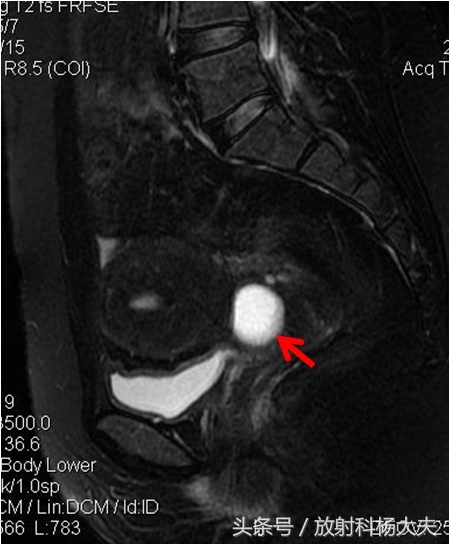

宫颈囊肿又叫宫颈纳氏囊肿,宫颈纳氏囊肿(可称“那囊”也有叫纳囊的)同宫颈糜烂、宫颈息肉一样,是慢性宫颈炎的一种表现。宫颈长3厘米左右,上端与子宫相连,下端在阴道的最深处。宫颈表面有腺体,可以分泌粘液。当子宫颈受到损伤或者发生炎症时,在修复的过程中,腺体的开口被新生的上皮策划堵塞,分泌的粘液不能顺利地流出来,就形成了所谓的“囊肿”!在核磁上,这种囊肿因为含水丰富,在T2WI上呈白白的高信号,里面信号很均匀,做了增强扫描,也不会发现里面有异常强化。当然,也可以分辨是否合并感染。周围有无肿瘤等等。

但在核磁上,准确诊断宫颈纳囊是第一步。因为还有一些非常少见的情况需要与宫颈囊肿区分,比如子宫内膜异位症发生在宫颈时也可表现为囊,但跟纳囊比较,其信号往往复杂,而且掺杂出血,容易鉴别。